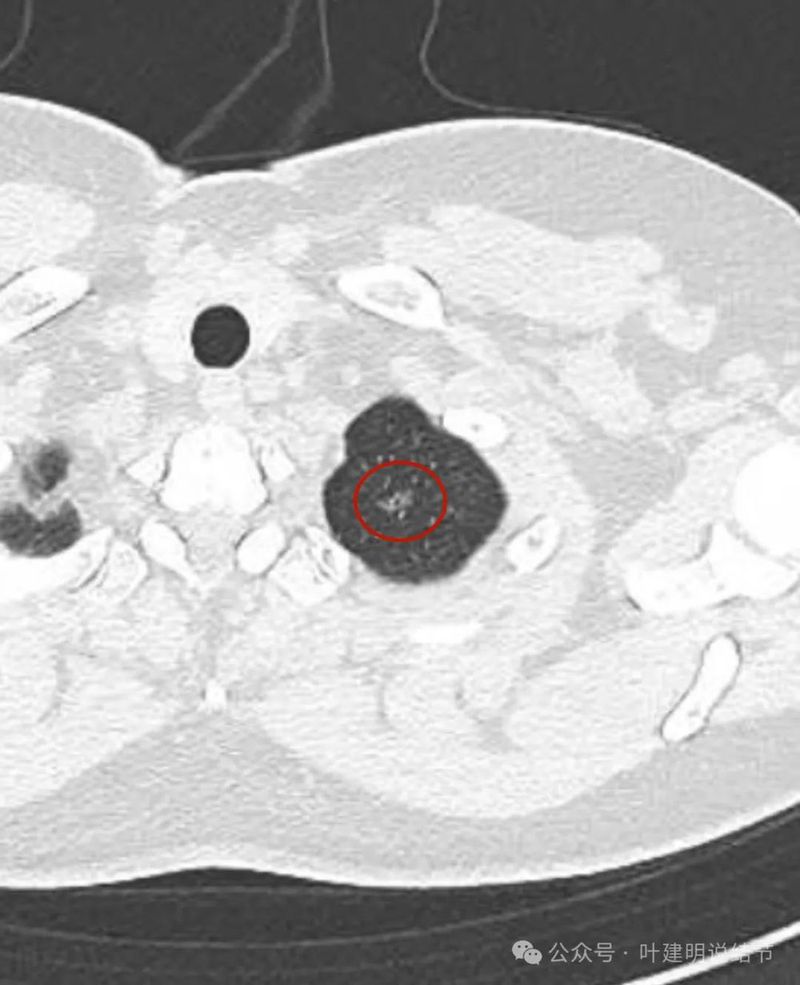

病灶出现 ,位于左肺尖,表面不平,中间有小空泡征,边缘欠光滑,灶内密度也欠均匀,整体轮廓与边界却较为清楚。